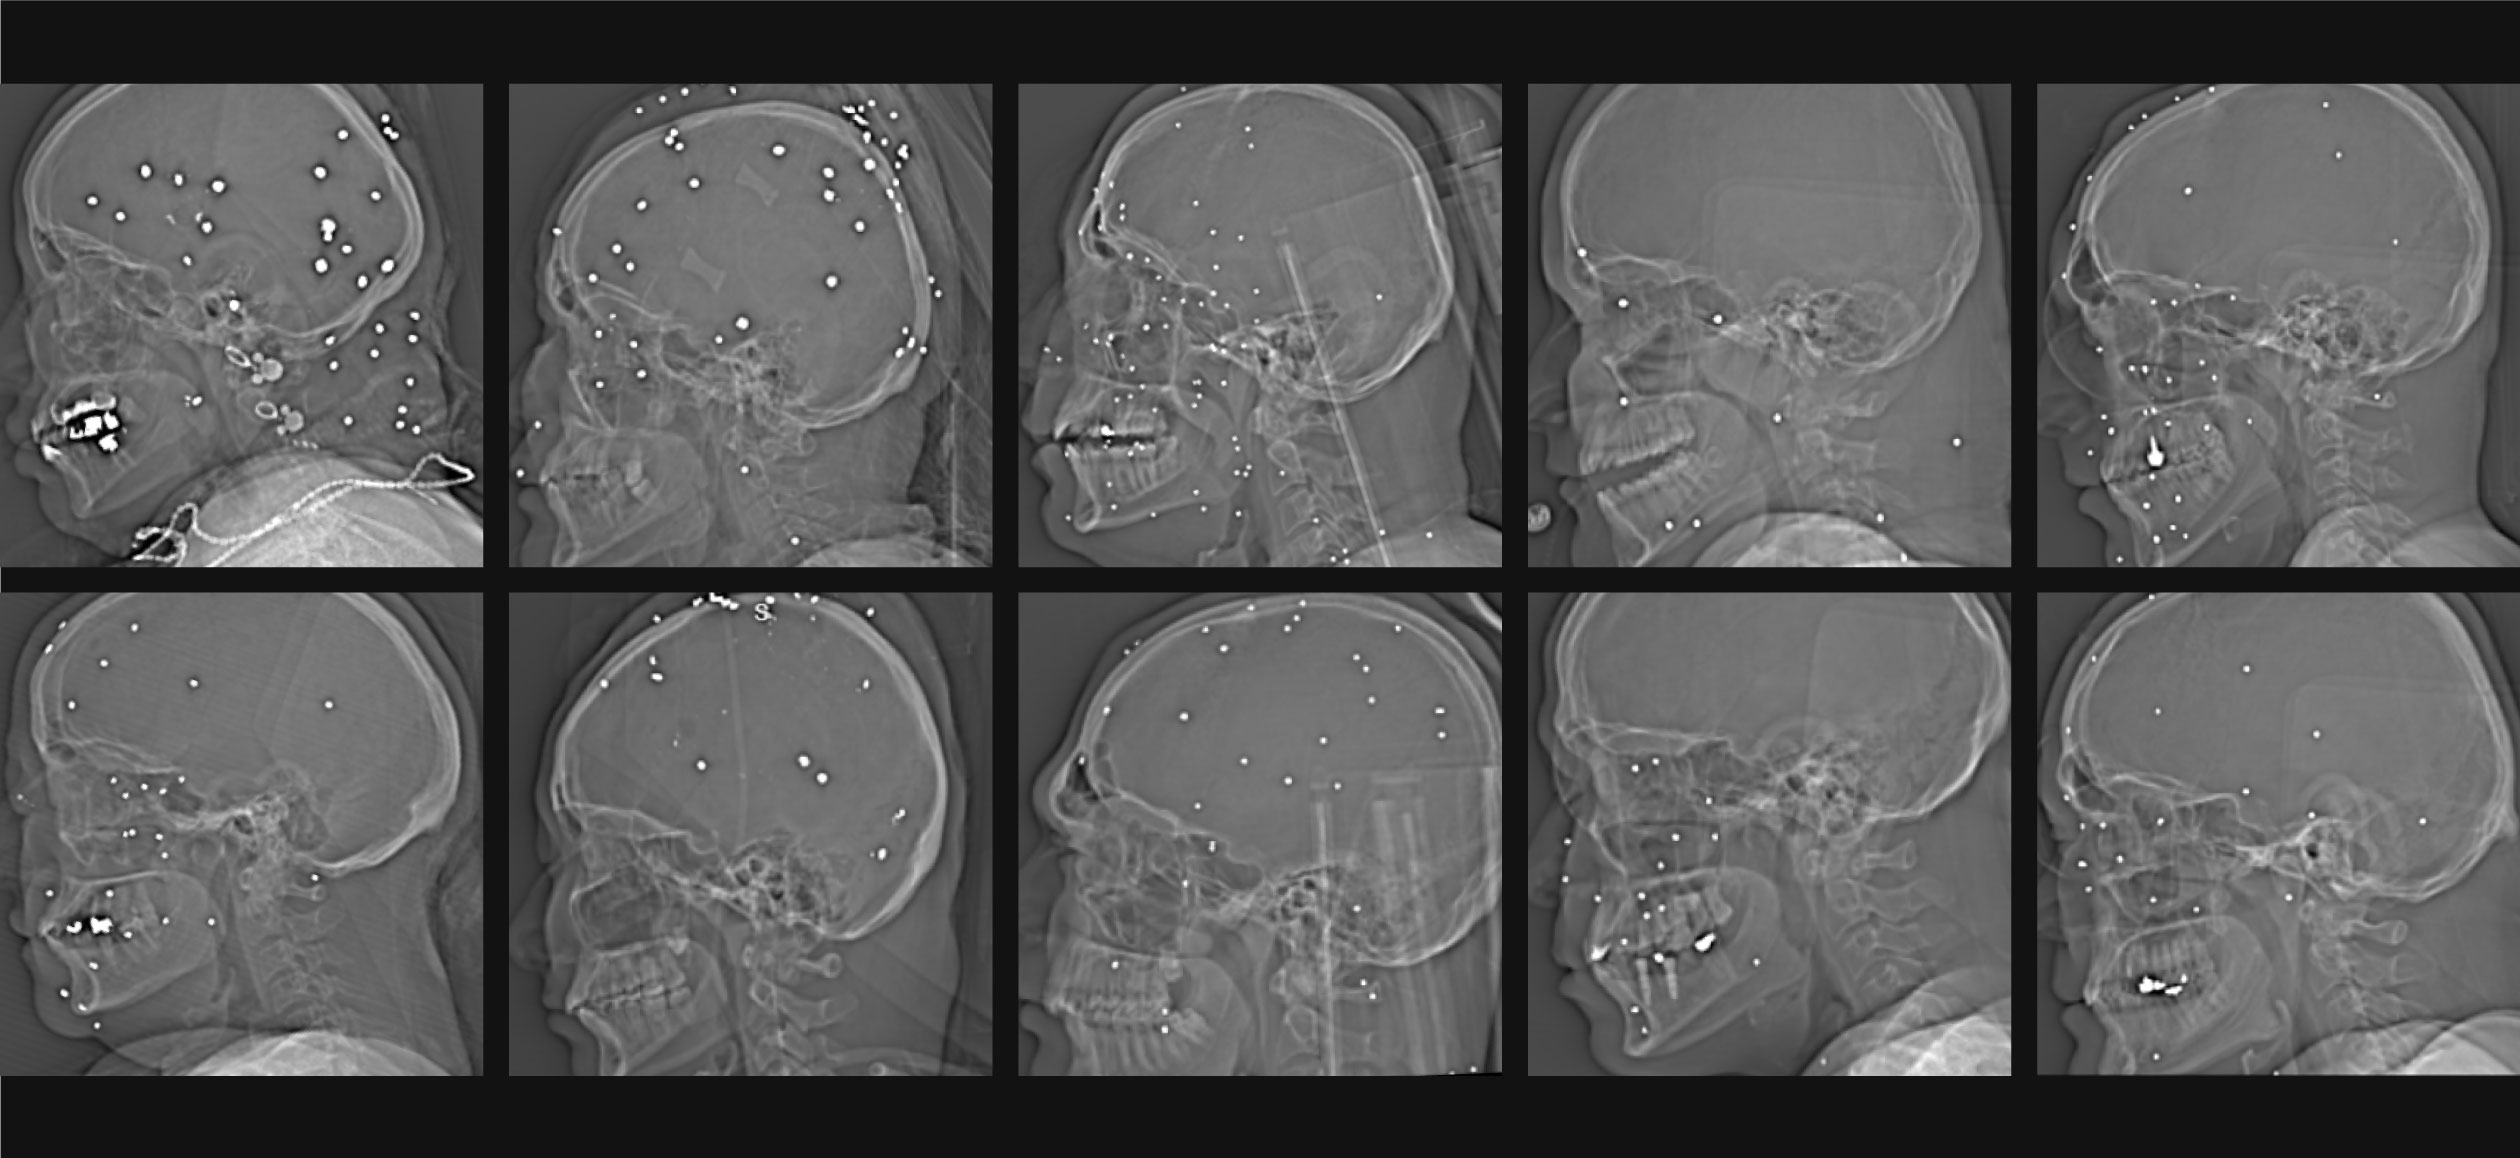

The images, secretly taken from a hospital in a major Iranian city during a single evening in January, show bullets lodged in the chests, skulls and abdominal cavities of demonstrators who had taken to the streets to protest against the ayatollah regime. Medical experts who reviewed the material said the wounds indicate that security forces aimed at protesters’ “center of mass” rather than using crowd control tactics.

In addition to high-velocity rifle rounds, the scans reveal close-range shotgun injuries, suggesting that police and members of the Islamic Revolutionary Guard Corps fired at detainees or individuals who had already been apprehended.

In total, 75 sets of medical images, primarily X-rays and CT scans, were shared with the Guardian from the single hospital. The grayscale images chronicle the lethal violence inflicted by the Islamic Revolutionary Guard Corps against protesters and bystanders, underscoring the intensity of the bloodshed within just a few hours at one mid-sized urban medical center.

The documentation adds to accounts previously given by doctors and protesters across Iran, who said security forces escalated from traditional crowd-dispersal methods to the use of assault rifles and high-caliber shotguns. The images show a pattern of gunshot wounds to the face, chest and genitals, a trend also reported during the 2022 “Women, Life, Freedom” protests that erupted after the death of Mahsa Amini in police custody.